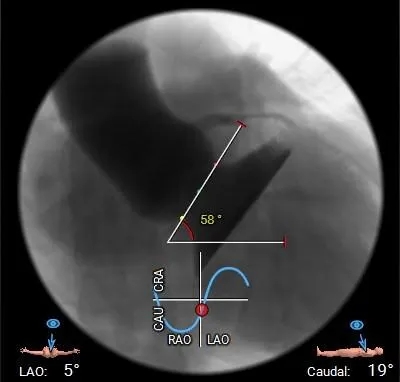

心脏角度

心脏角度:58°